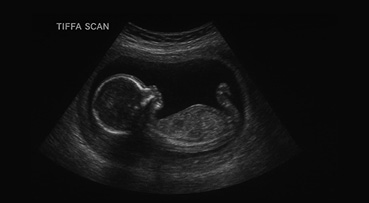

What is a Tiffa Scan

A TIFFA scan (Targeted Imaging for Fetal Anomalies) is a detailed ultrasound test which was done during pregnancy to check how your baby is growing and developing inside the mother’s stomach. It helps doctors see if all your baby’s organs through an ultrasound technique like the heart, brain, spine, kidneys, and limbs are forming normally or abnormally.